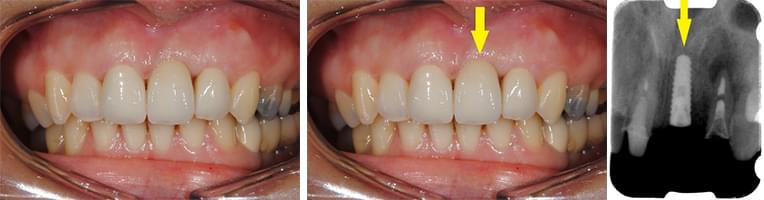

下の写真ですが、上顎前歯2本のうち向かって右の歯がインプラントなのですが、歯肉がわずかに上にあがってしまい、全くの左右対称にはできずに、右の歯の方が少し長くなってしまっています。

これなどは、もう少し長くなっていますが、口唇を上に引っ張らない限りはそれが見えません。

以下も、一見それほど問題にならない程度には仕上がっていますが、隣の歯との間、歯肉の間に空間が残っており、中にはご満足いただけないこともあります。幸いにして、この患者様方には、あらかじめ、見た目についてのご説明をさせていただいた上で、治療を始めていますので、ご納得いただいております。